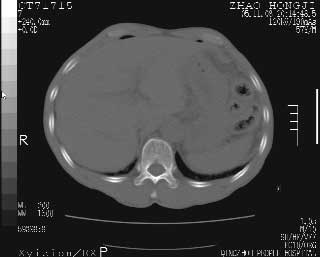

临床资料:男性,57岁,上腹部疼痛并5天,突然加重并延及全腹伴恶心5小时入院。胰淀粉酶化验在正常范围。检查:腹肌紧张,全腹压痛、反跳痛,尤以右上腹部为著。肠鸣音减低。血常规:wbc14.6x10/9, n:11.3x10/9 ,血压:135/90mmhg. 胸部透视:腹部肠腔轻度张气,未见其它异常改变。

肝右前缘少量积气,其他未见明显异常.考虑上消化道穿孔.

小网膜囊积气液,胃壁僵硬。考虑胃穿孔。

小膜网膜积液,肝缘气腹征,上消化道穿孔。

肝缘见少许气体,胰尾部见少许气体包饶(蓝色圈),12指肠上部或球部邻近胆囊周边也可见少许气体影(黄色圈),并忖托出胆囊壁,12指肠远段肠道内未见明显气体(白色箭)。

肝脏前缘见少量积气、胰尾部见少许气体包饶,肾前筋膜未见增厚,临床淀粉酶不高,意见:上消化道穿孔。

入院3小时后行剖腹探查术,见腹腔内大量脓性混浊液约1000ml,十二指肠球部溃疡穿孔,溃疡面约2.5x2cm,穿孔直径约0.6cm。胃内容物外益,周围组织炎性水肿明显。行十二指肠穿孔修补术。术后诊断:

1、十二指肠溃疡穿孔

2、弥漫性腹膜炎

对于少量的腹腔游离气体,ct检查较普通透视有绝对的优势,它不仅可以看到肝脏前上缘的气体,而且还能够看到小网膜区的游离气体。从而可以肯定诊断。各位分析战友的很好,感谢大家的参入!